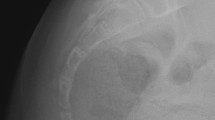

In the 37 survived kaolin-induced rabbits, before the week 6 after surgery, even minor curve of spine was found in none. But from the week 6 to 12, scoliosis formation was detected in 73.0% (27/37) of the experimental rabbits and the final Cobb angle was up to 27.4 ± 10.0° (15–59°) (Fig. 1, Table 1). These 27 rabbits were involved in group S, and the other 10 without spinal curve were in group Non-S. In the control, scoliosis formation was observed in none.

Posterior-anterior radiographs of the spine and scoliosis development (Rabbit 21#). Preoperative coronal imaging of spine (A). Postoperative 6-week, a tiny thoracic curve appearance and the Cobb angle was 12° (B). Postoperative 12-week, the thoracic scoliosis developed to 54° (C). Post-anatomic observation of the thoracic scoliosis and the apical vertebra was marked by the white arrow (D).